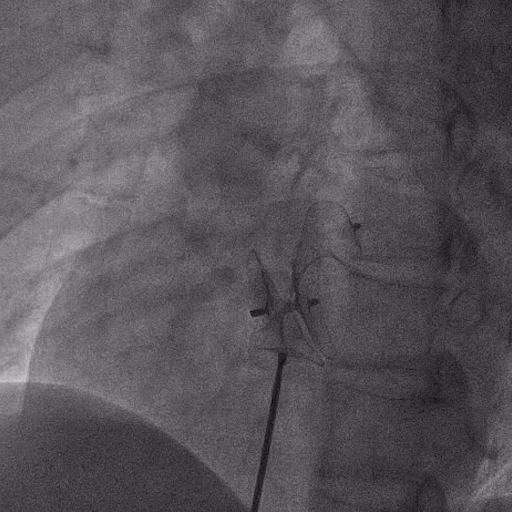

在獲得患者同意后,1月12日,尚福軍主任為患者進行了PFO封堵術(shù)。術(shù)中造影可見封堵器殘余漏,尚福軍主任用精湛的技藝,順利通過封堵器殘余漏裂縫,將右心導管從右房送入左房,且順利到達肺靜脈;遂行卵圓孔未閉封堵術(shù)后殘余漏再次封堵;且完美釋放PFO封堵器,可見兩封堵器呈“馬蹄蓮”狀,再次術(shù)中造影未見殘余漏。